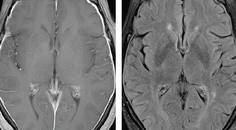

Meningeal Enhancement Seen on Workup for Memory Loss

Nima Khosravani, MS; Anamaria Shanley, MSN, ARNP-BCNima Khosravani, MS; Anamaria Shanley, MSN, ARNP-BC